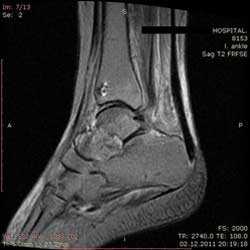

Рис4. а. на КТ перелом таранной и большеберцовой костей, б. на МРТ перелом таранной кости